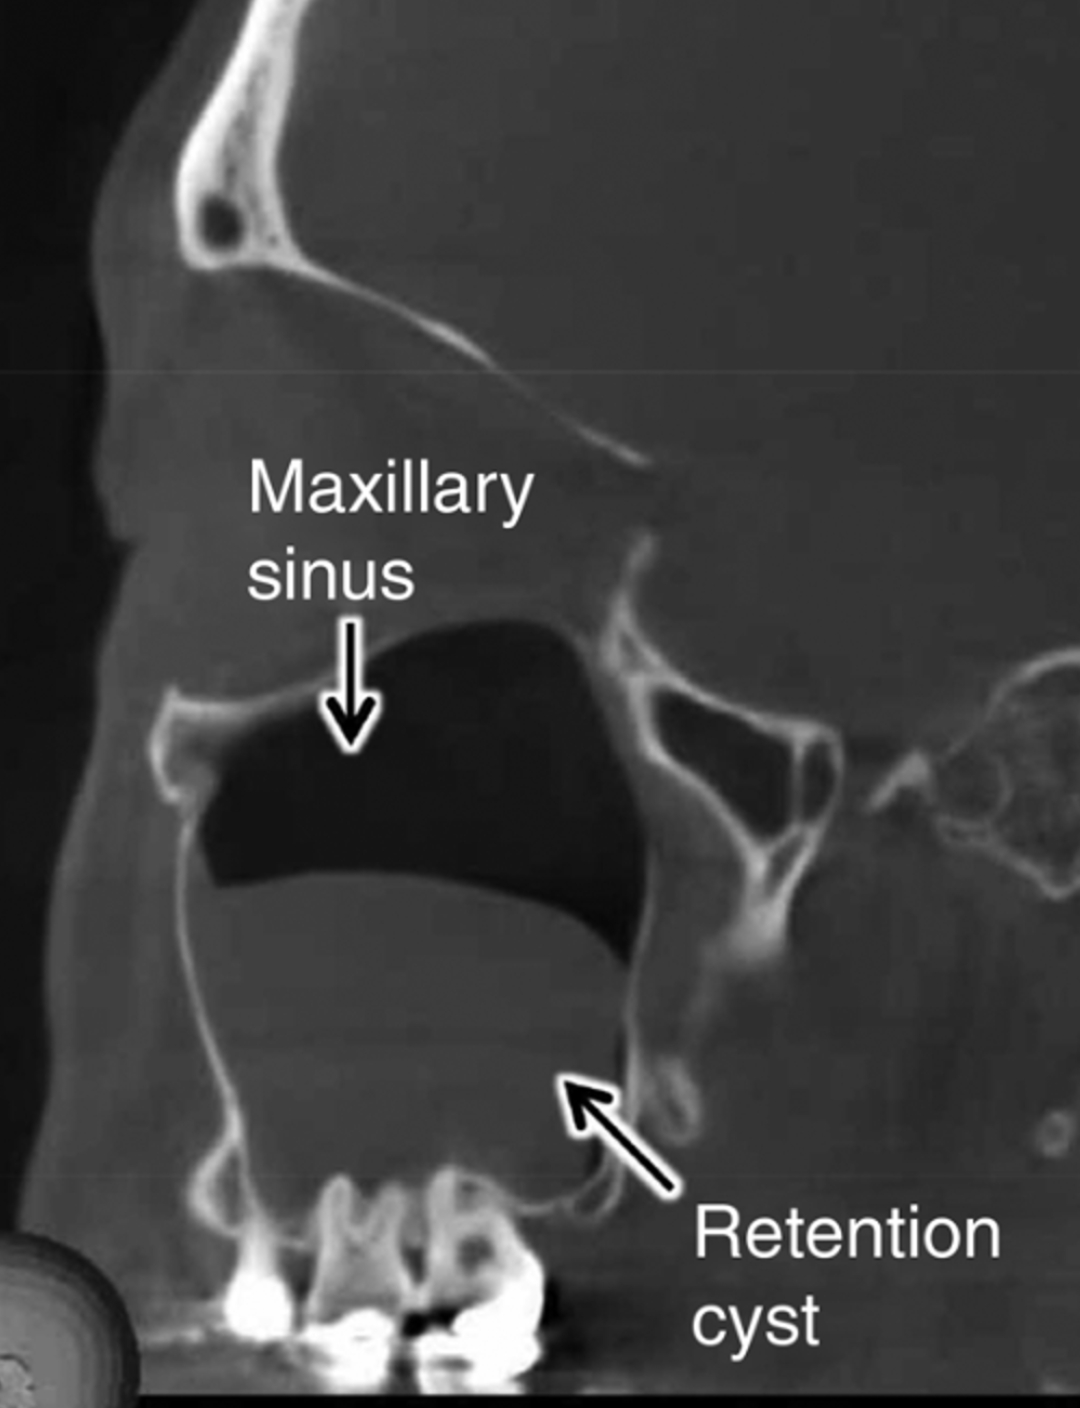

Възможно ли е подобно изглеждаща "маса" в синуса да е причинена от гранулом и дали ще изчезне след лечението на гранулома?🤔

Снимката, която слагам е примерна от интернет, на моето cbct левият синус е ок, а десният изглежда запълнен изцяло от нещо подобно, което най-вероятно не е полип. Оттам нататък дали е киста или друго, не можаха да ми кажат. Препоръчаха ми консултация и с лицево-челюстен хирург. Да подчертая, че нямам абсолютно никакви симптоми откъм синуса, нямам запушен нос, изкривена носна преграда, секрети, главоболие, подутини и др. подобни. Бях на прегледа заради бъдещ имплант, заради който ще се наложи и синус лифт.